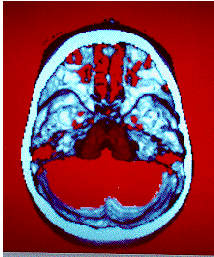

Octree Encoded Images from the RAD program:

Ventricular System inside the Skull.

Thalami and base of the Skull.